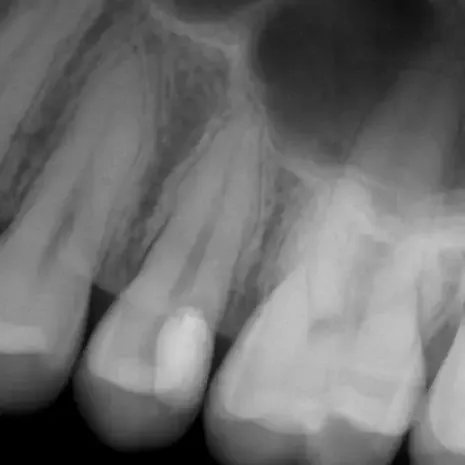

Fall 5: Starke Wurzelkrümmung

Endodontie Fall 5: Starke Wurzelkrümmung

Vor der Behandlung